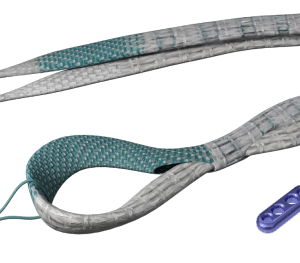

• Một ống nhựa để lót vỏ bọc của gân bị đứt có vòng chỉ gắn ở đầu ống nhựa, cho phép đầu dò, giá đỡ kim và gân luồn qua vỏ bọc gân từ gần đến xa mà không bị kẹt.